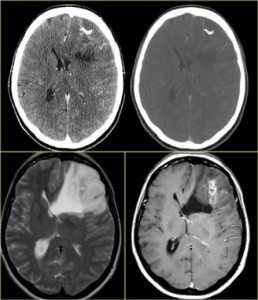

- Кальцификация видимая при КТ и хуже МРТ головного мозга - олигодендроглиомы (90%), краниофарингеома (90%), астроцитомы (20%), эпендимома (50%), папиллома сосудистого сплетения (25%), ганглиоглиома (40%), менингиома (20%), редко - метастазы, хордомы, хондросаркомы

МРТ и КТ головного мозга. Кальцинаты в олигодендроглиоме